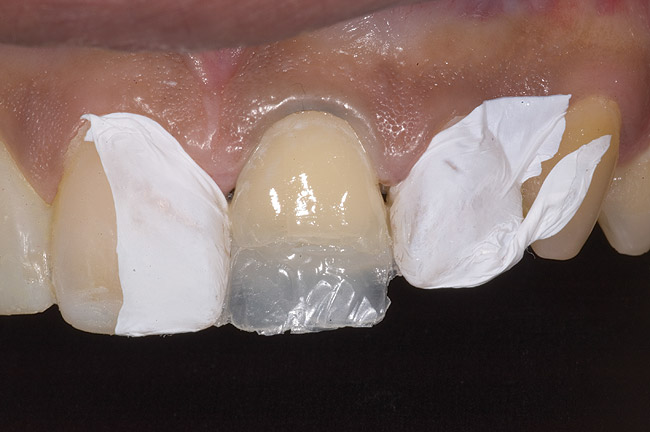

Figure 9: Tooth No. 9 minimally prepared for resin layering on the labial surface.

Figure 9

Figure 10  Tooth No. 9 with no preparation on the palatal surface to restore lost form with bonding resin.

Figure 10

During the next appointment, a palatal index of the approved provisional was fabricated with putty silicone. This enabled the clinician to precisely build the lingual surfaces and incisal edges of teeth Nos. 6 through 11. The provisional mock-up resin on No. 9 was removed, and the underlying labial tooth was roughened with an abrasive diamond bur. No tooth structure was removed from the palatal surface, and unsupported enamel was rounded off from the labial. An ultrathin dry cord was placed in the gingival sulcus on No. 9 (Figure 9 and Figure 10). Teflon tape was used to isolate No. 9 from adjacent teeth. Then 37% phosphoric acid was used to totally etch the labial surface for 10 seconds and the palatal surfaces on No. 9 for 5 seconds. Single bond was applied and spread uniformly across the tooth and light-cured for 20 seconds.